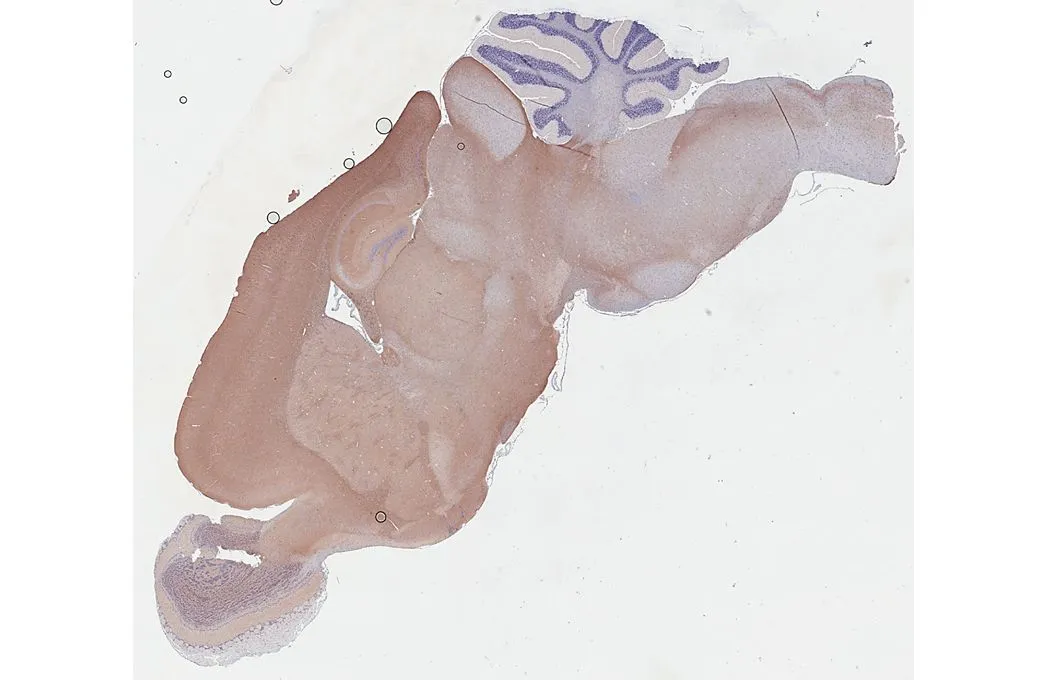

![BASP1 antibody [HL3760] detects BASP1 protein by immunohistochemical analysis. Sample: Paraffin-embedded mouse brain. BASP1 stained by BASP1 antibody [HL3760] (GTX641959) diluted at 1:250. Antigen Retrieval: Citrate buffer, pH 6.0, 15 min BASP1 antibody [HL3760] detects BASP1 protein by immunohistochemical analysis. Sample: Paraffin-embedded mouse brain. BASP1 stained by BASP1 antibody [HL3760] (GTX641959) diluted at 1:250. Antigen Retrieval: Citrate buffer, pH 6.0, 15 min](https://www.genetex.com/upload/website/prouct_img/normal/GTX641959/GTX641959_T-45670_20250529_IHC-P_M_25061003_146.webp)